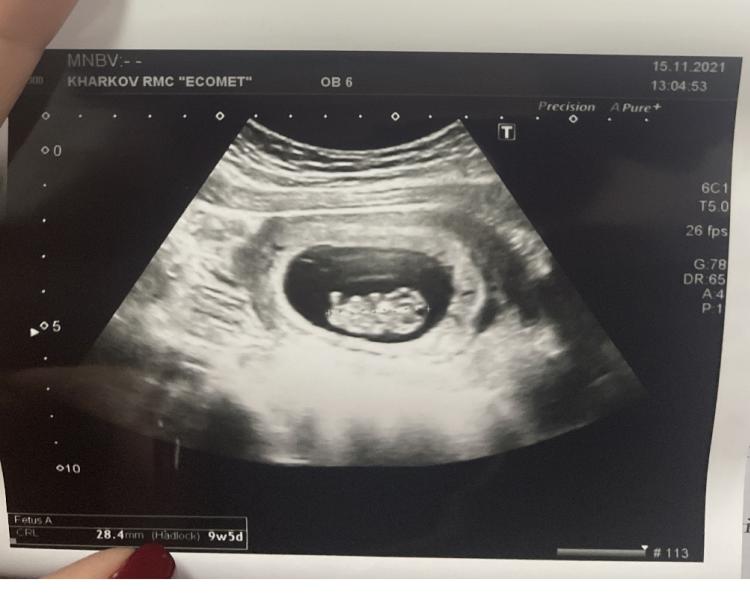

Вчера ходила на узи, чувствовала, что надо пойти посмотреть, дали фото… теперь хочется всем рассказать, не знаю как терпеть, раньше вроде «ну че там ещё говорить», а теперь вот, у нас даже фотка есть 😂 говорю, хочу создать чат, добавить туда всех родителей бабушек и скинуть, муж: «прошу, только не общий чат» 😂